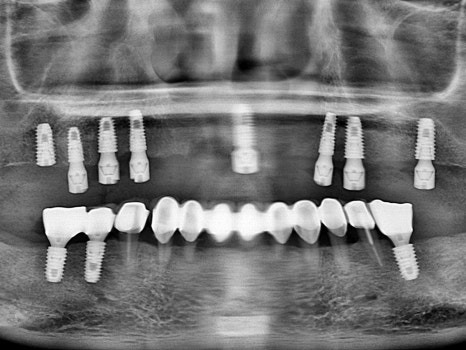

수술 후

8개의 전체임플란트를

하루에 바로 수술할 수 있었고,

병원 내의 디지털기공소에서

바로 임시치아를 제작하였습니다.

수술 전

수술 1일 후

하루만에 위턱 전체 치아가 생겨서

식사가 바로 가능하시게 되자

환자분은 너무 놀라워하시고 좋아하셨습니다.